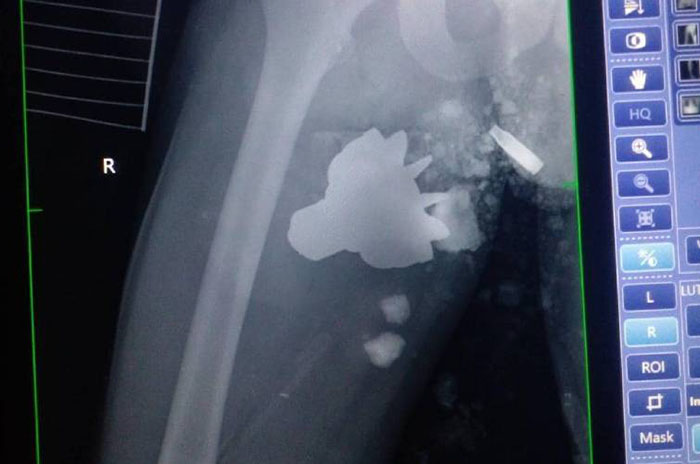

Хвостовик міні виявили під час рентгенівського обстеження пораненого.

Частина вибухівки застрягла в нозі бійця, повідомляють в Генеральному штабі Збройних Сил.